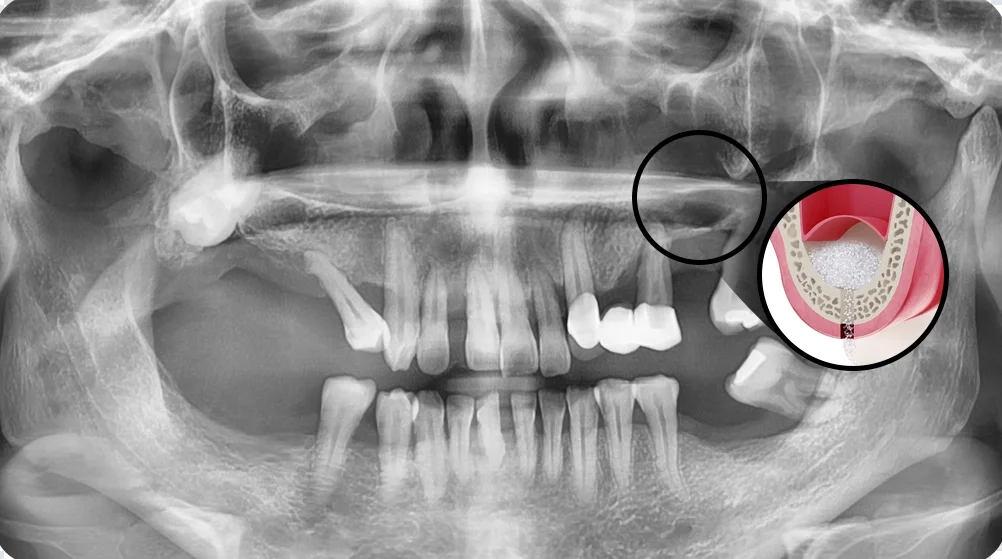

천안임플란트 서울비디치과의 상악동 거상술 X-ray

뼈이식·상악동 거상술이 필요한 고난도 임플란트 케이스

고난도 케이스는 수술보다 진단과 계획의 비중이 커집니다.

환자분의 케이스의 위험요인이 무엇인지, 어떤 단계로 진행되는지, 관리 계획까지 포함되는지 확인하는 것이 안전합니다. 필요 시 협진과 응급 대응도 함께 보셔야 합니다.